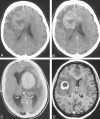

CNS lymphoma consists of 2 major subtypes: secondary CNS involvement by systemic lymphoma and PCNSL. Contrast-enhanced MR imaging is the method of choice for detecting CNS lymphoma. In leptomeningeal CNS lymphoma, representing two-thirds of secondary CNS lymphomas, imaging typically shows leptomeningeal, subependymal, dural, or cranial nerve enhancement. Single or multiple periventricular and/or superficial contrast-enhancing lesions are characteristic of parenchymal CNS lymphoma, representing one-third of secondary CNS lymphomas and almost 100% of PCNSLs. New CT and MR imaging techniques and metabolic imaging have demonstrated characteristic findings in CNS lymphoma, aiding in its differentiation from other CNS lesions. Advanced imaging techniques may, in the future, substantially improve the diagnostic accuracy of imaging, ultimately facilitating a noninvasive method of diagnosis. Furthermore, these imaging techniques may play a pivotal role in planning targeted therapies, prognostication, and monitoring treatment response.